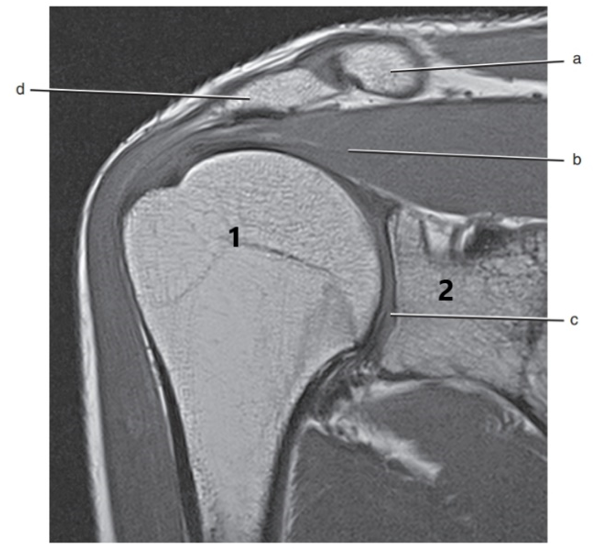

What anatomy is # 1 ?

Humeral head

What is letter c ?

Superior glenoid labrum

What is letter B pointing to ?

Humerus

What is letter C pointing to ?

Coracoid process

What is # 1 ?

What is # 2 ?

Acromion Process

What is letter d ?

Acromioclavicular ligament

Subscapularis tendon

What is letter b ?

Supraspinatus muscle

Posterior glenoid labrum